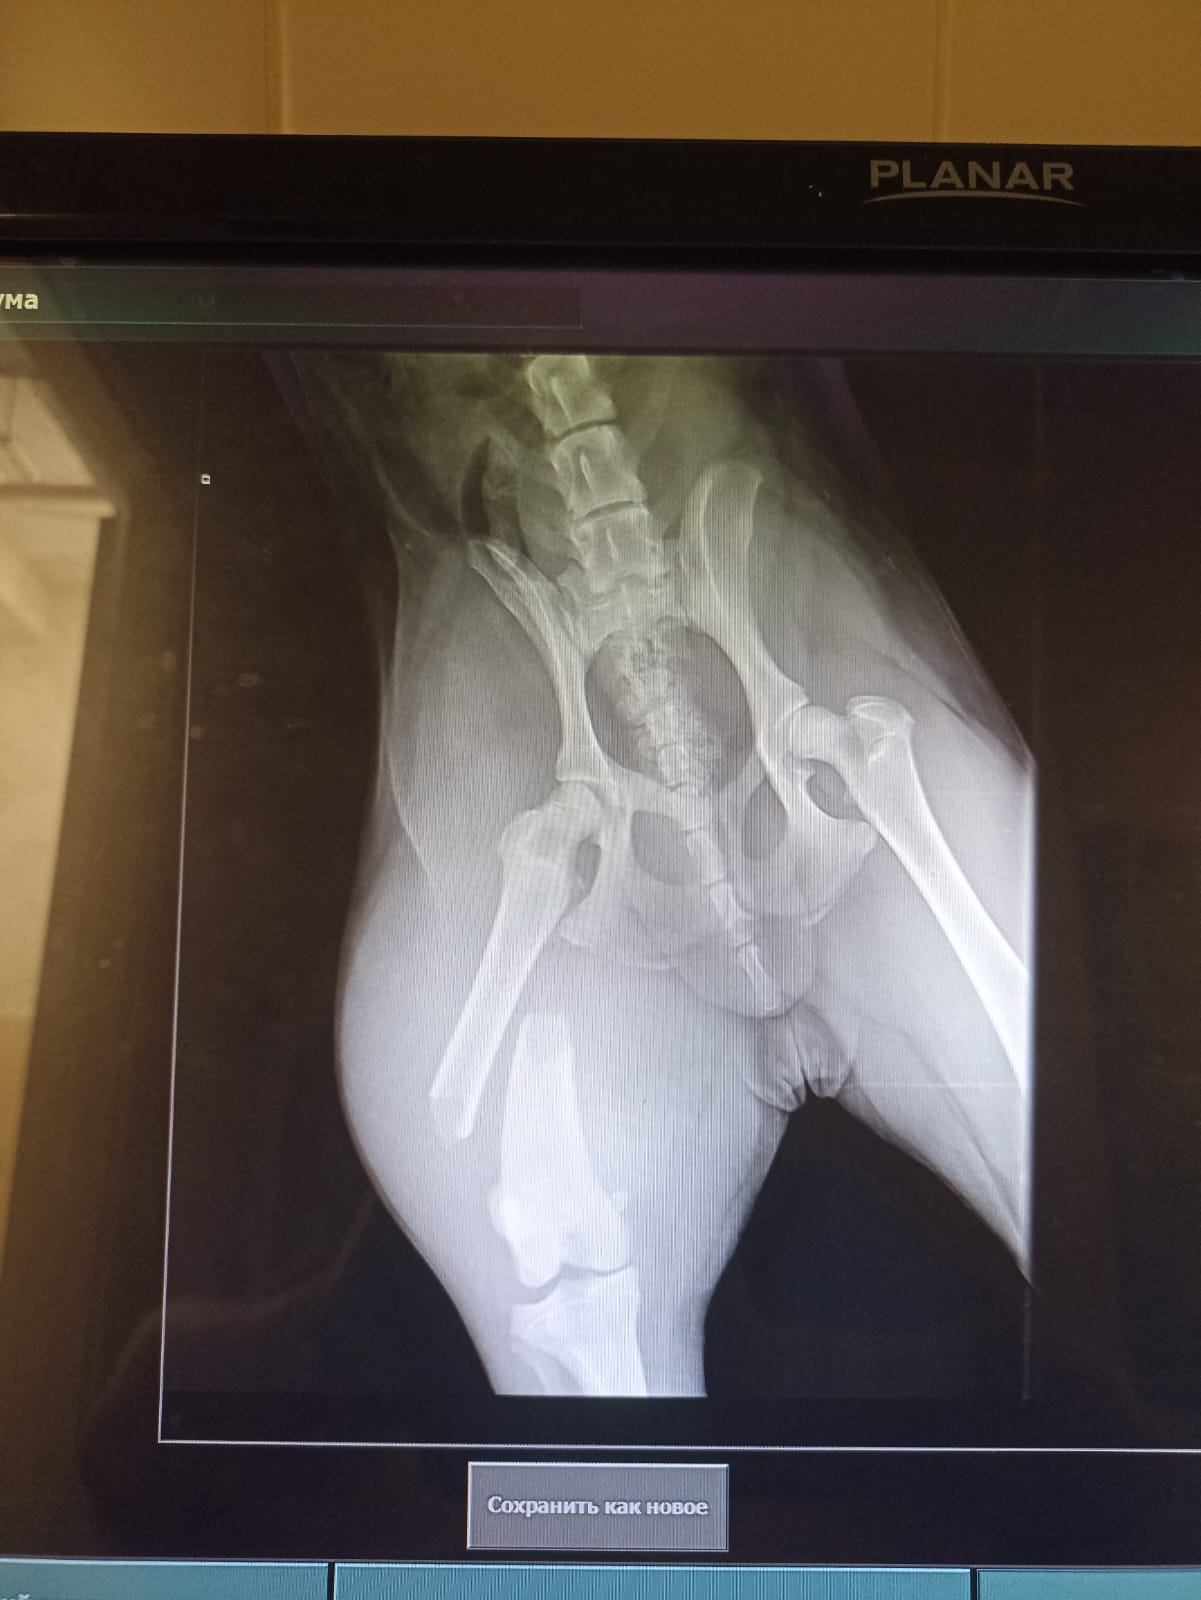

Через 2 недели контрольный рентген и снятие швов.